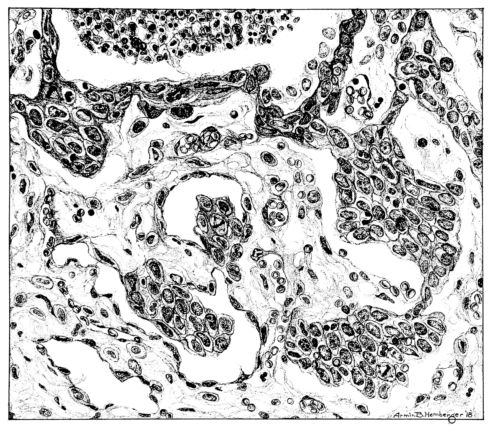

A more striking picture, however, even than this aplastic alveolar exudate appears in the terminal bronchioles. In many instances, these are conspicuous on account of their size, for they are dilated to form prominent, often irregular, sacs (Fig. XV). The distention of these terminal bronchioles may be so great that the surrounding alveoli are compressed. What makes them even more conspicuous is their lining, once epithelium, but now a swollen, thick, homogeneously staining material, with complete loss of architecture; the material forms (with hematoxylin and eosin) a red band limiting the lung tissue and sharply demarcating it from the exudate within the bronchioles (48, 92). However, this ribbon of red, often thickened by fibrin deposition, is not always pure, for bacteria thrive in the dead tissue. They occur singly, paired, in chains, and also as circumscribed, dense masses which in size and position, simulate nuclei (162) (Fig. XVI). This same hyalinization of the epithelium, it will be recalled, occurs in the larger bronchi (Fig. V), and there, too, bacteria frequently develop in the dead tissue (Fig. VIII). In the smallest bronchiolar ramifications, acute epithelial necrosis is not infrequently encountered, even when the surrounding lung tissue is relatively normal (Fig. XVI). That the process does not stop with the epithelium, but, as in the larger bronchi, may extend through the entire structure of the bronchioles, is manifest. Even the alveolar walls may be involved and frequently homogeneous pink or red bands, now the phantom of the former viable lung tissue, mark the presence of the old wall of the alveolus (Fig. XVII). Occasionally, some architecture remains in this pink ribbon and then the involvement seems to be primarily in the vessels of the wall. Not all the vessels are involved, and next to a hyaline thrombus in one, there may be fresh blood, usually red blood, in its neighbor. The alveolar epithelium is usually denuded and thus accentuates the intensity of the change.

The acute death which involves the tracheal, bronchial, and bronchiolar epithelium and which may extend beyond the epithelium into the walls of these structures and kill en masse the walls of the alveoli, is a lesion which does not occur in other types of acute pulmonary infection. However, in influenza, as after exposure to pulmonary irritating gases, it is the lesion of characterization (158,159). The effects of this change, of course, where it involves 22the alveolar wall, will vary with the extent of the process; but given an absolutely necrotic wall, as yet unstrengthened by inflammatory reaction, an expected result would be its rupture with respiratory movement. The point of rupture is important, but where so many alveoli are involved, disturbance of continuity will occur, occasionally in such position that the result will be the escape of air into the interstitial tissues.[7] There is ample evidence that this happens. Indeed, among the clinical manifestations of the disease, interstitial emphysema of the lung spreading through the fascial planes to the subcutaneous tissues of neck and thorax is well known; the phenomenon is more frequent and extensive in influenza than in any other disease (8, 17, 52, 143).